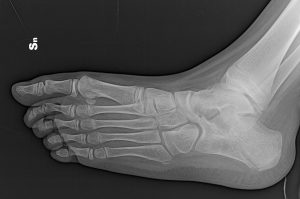

La diagnosi viene solitamente confermata con la radiografia del piede che deve essere eseguita in tre proiezioni: antero-posteriore, laterale in carico, obliqua a 45° (fondamentale per le sinostosi calcaneo-scafoidee) e la proiezione calcaneare di Harris (fondamentale per la sinostosi astragalo-calcaneare).